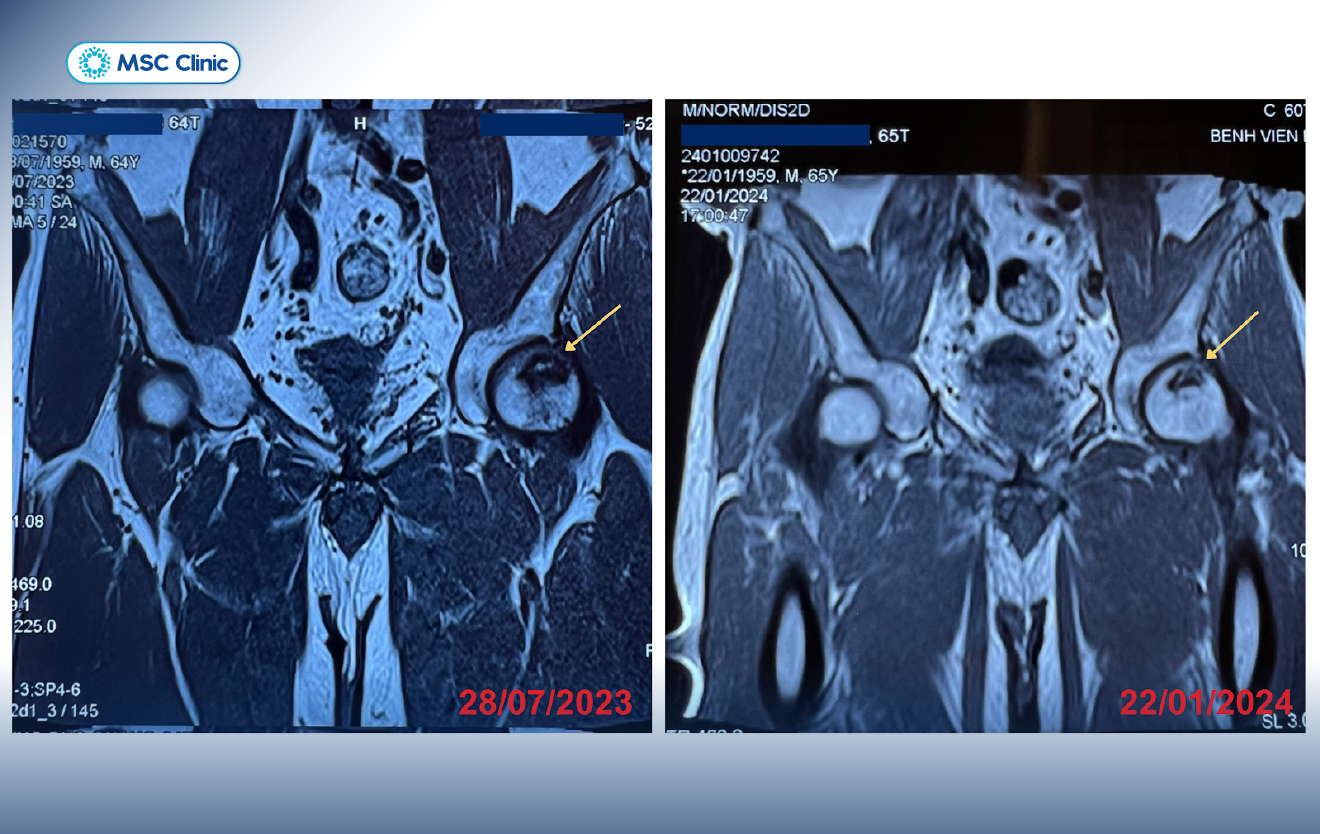

Ông Phùng Đức Quang là một ca bệnh khó nhưng đã được chuyên gia tại Phòng khám Đa khoa MSC điều trị hiệu quả. Từng bị hoại tử chỏm xương đùi bên phải, sau 5 năm chỏm xương đùi bên trái của ông Quang cũng xảy ra tình trạng tương tự. Sau 6 tháng điều trị, ông và gia đình nhận tin mừng tổn thương đã có cải thiện tích cực và đang tái tạo lại cấu trúc nhanh chóng.

Chỏm xương đùi bên trái bị hoại tử độ 2 đã có sự cải thiện rõ rệt